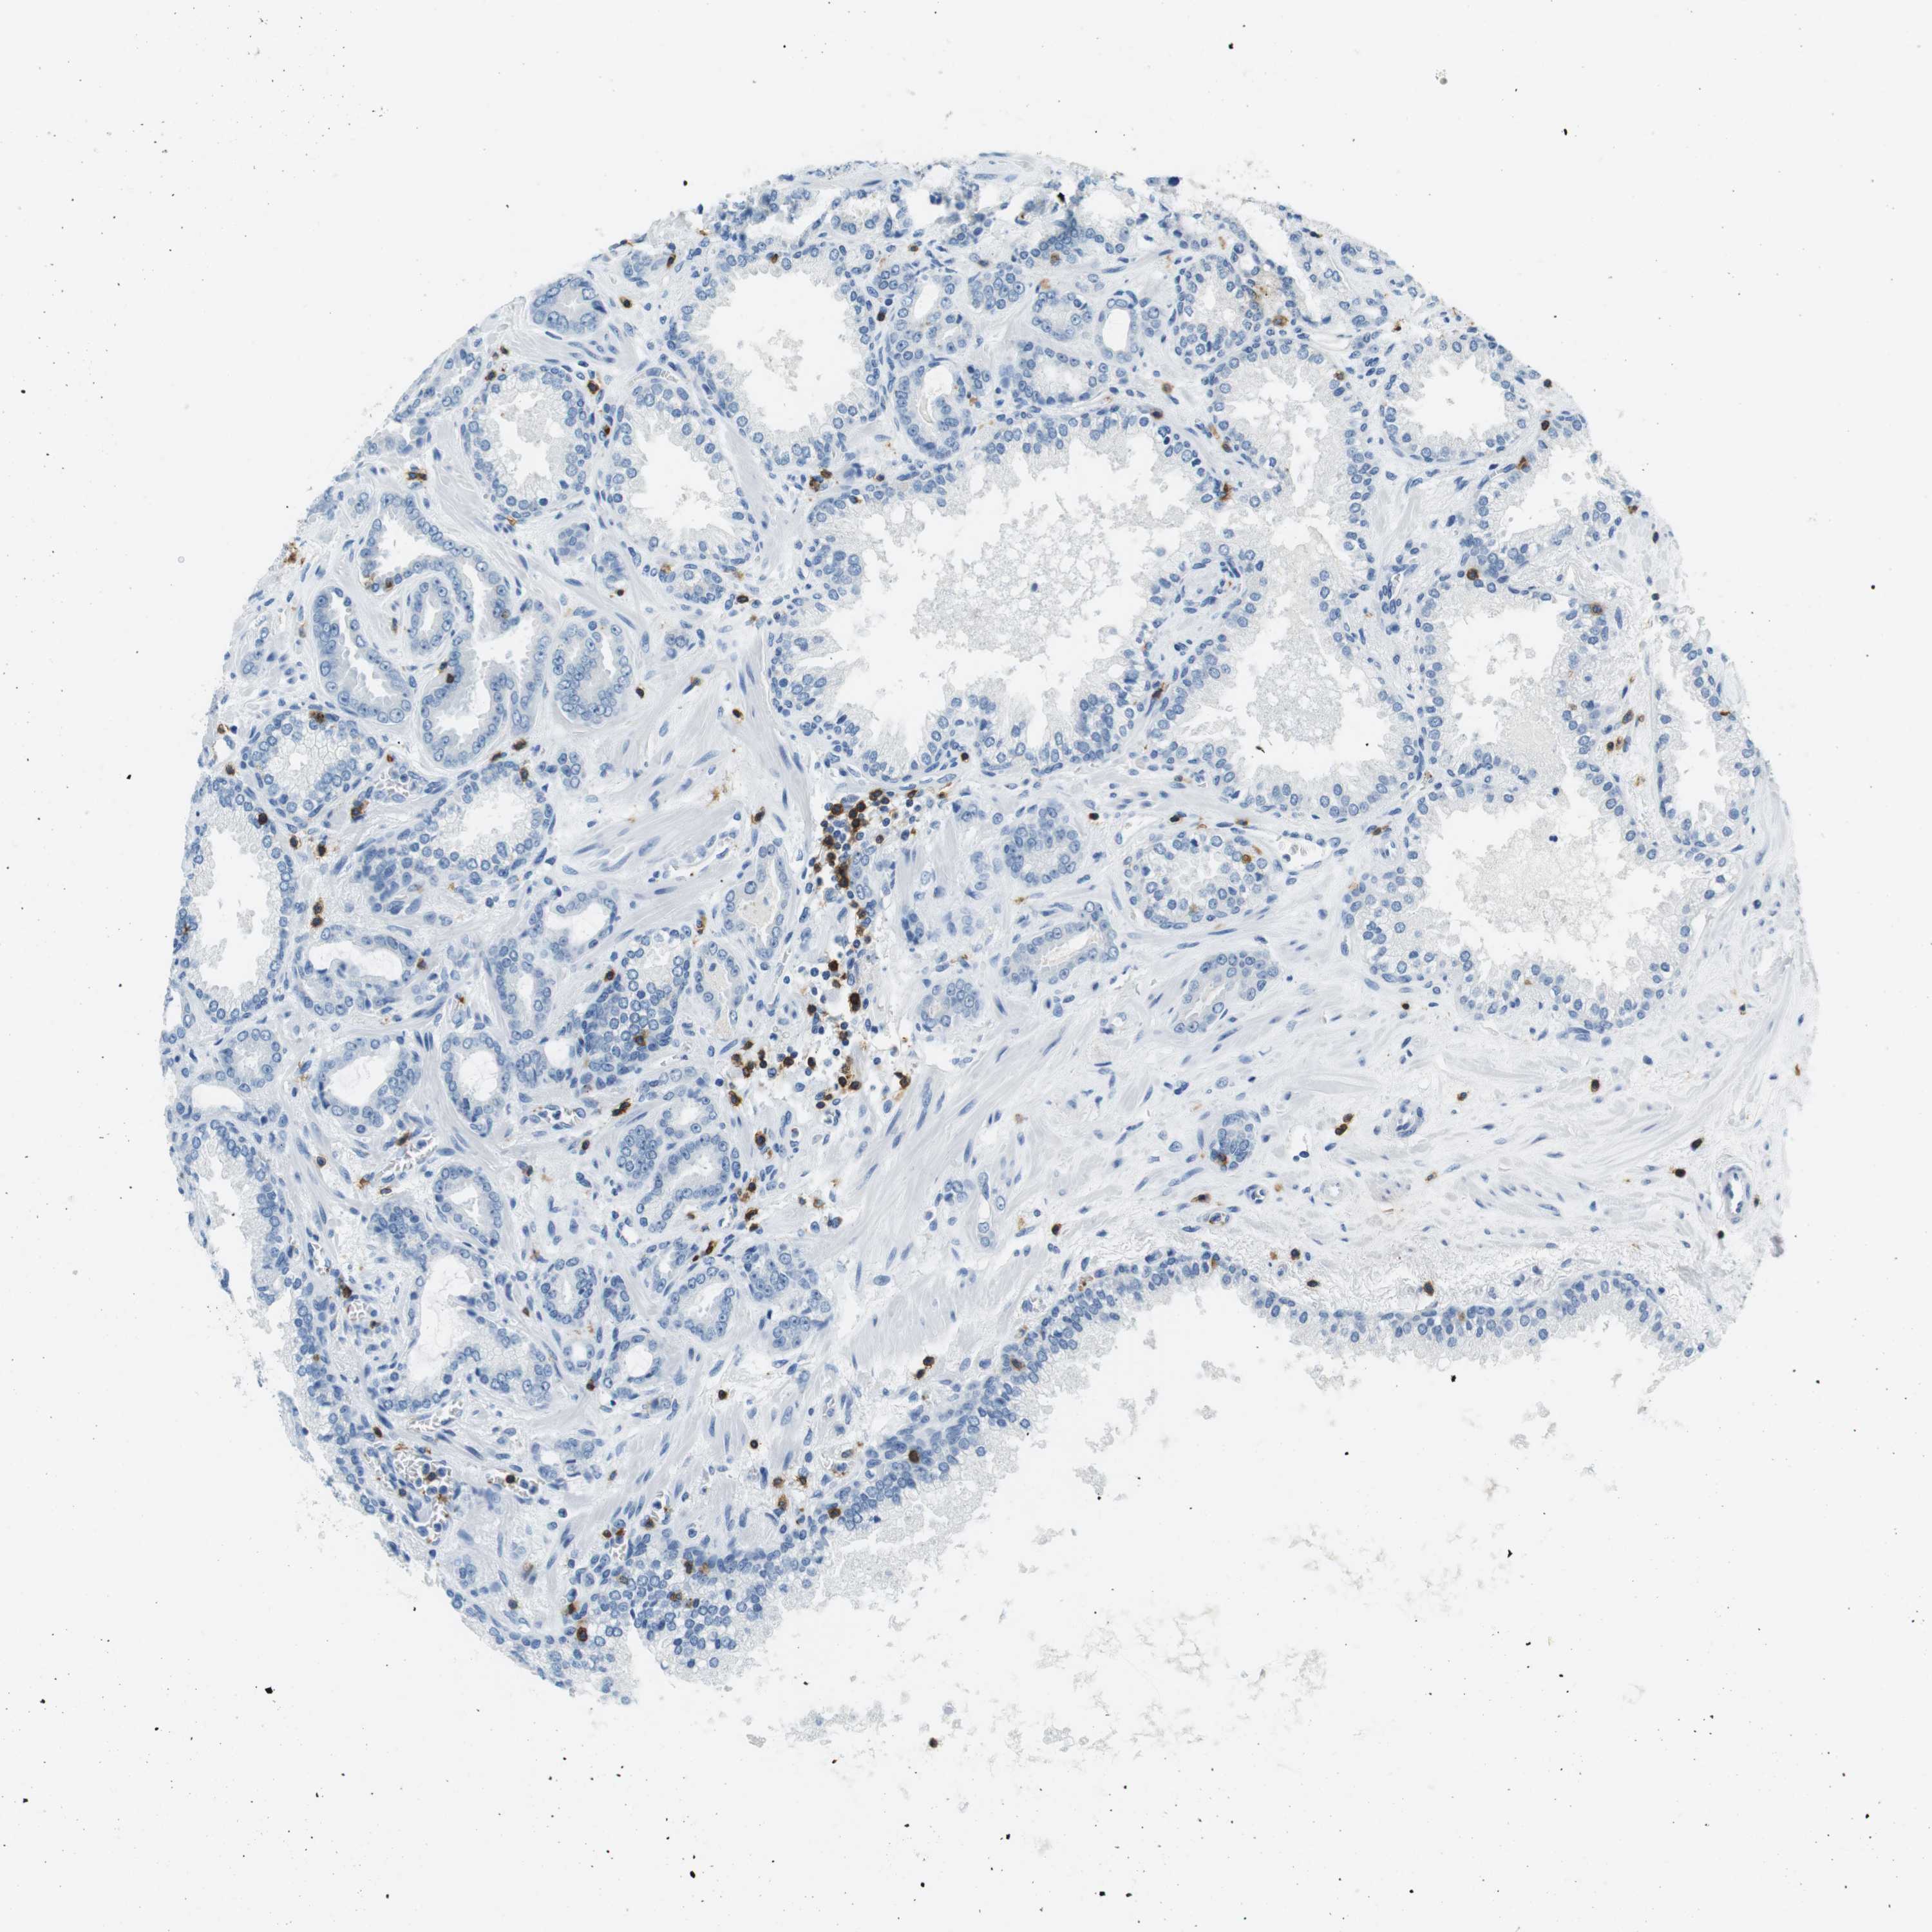

PROSTATE CANCER - Protein expressioni

A mouse-over function shows sample information and annotation data. Click on an image to view it in a full screen mode. Samples can be filtered based on level of antibody staining by selecting one or several of the following categories: high, medium, low and not detected. The assay and annotation is described here.

Antibody stainingi

Antibody staining in the annotated cell types in the current human tissue is reported as not detected, low, medium, or high, based on conventional immunohistochemistry profiling in selected tissues. This score is based on the combination of the staining intensity and fraction of stained cells.

Each image is clickable and will lead to virtual microscopy that enables deeper exploration of all samples and also displays staining intensity scores, fraction scores and subcellular localization as well as patient and tissue information for each sample.

Antibody HPA011157

Antibody CAB002223

Antibody CAB012978

Antibody CAB079960

Staining

High

Medium

Low

Not detected

Intensity

Strong

Moderate

Weak

Negative

Quantity

>75%

75%-25%

<25%

None

Location

Nuclear

Cytoplasmic/membranous

Cytoplasmic/membranous,nuclear

Adenocarcinoma, Low grade

Adenocarcinoma, High grade

Adenocarcinoma, Medium grade

Adenocarcinoma, NOS